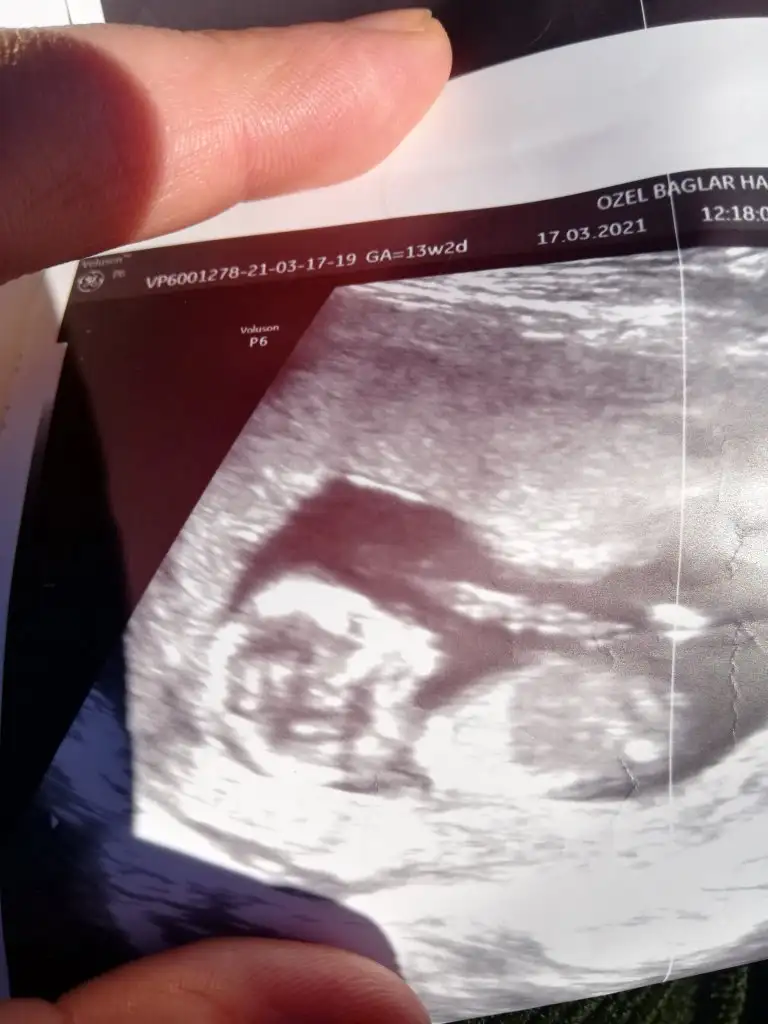

dr soylemeden siz gorun genital nub teorisi ( bebegin cinsiyeti)

Canım 2 hafta önce doktor 11 haftalıkken erkek dedi 13 hafta başka doktora gittim oda bu hafta belli olmz ama aynı senn yöntemle paralel dedi kıza benziyor dedi yani nub yöntemini kullndı kime inannacagımı şaşırdım paraleldi gerçekten 13. Hafta da 11 dede dikti canım hangisi yanılıyor bilmiyorum

Ikra meyra Ikra meyra 13+1 haftalık karından ultrason görüntülerini yorumlayabilir misin?☺️🙏